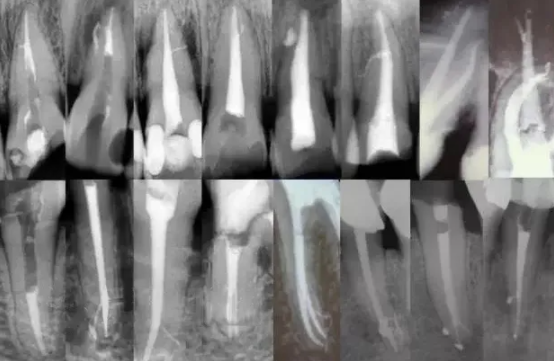

一个牙齿的根管治疗难易程度不单单是根管的弯曲、细小、牙位、是否再治疗决定的,开髓的直线进入和根管口的预先恰当处理可以简化很大的难度,开髓是根管成败的基础。

对于弯曲根管冠部的直线入口就显得尤为重要,冠部良好的直线入口可以避免侧穿、台阶、遗漏根管等问题的发生,冠部直线入口形成的良好情况,取决于医生的理念和合理的器械选择。开髓孔的大小不是由医生和患者的意愿决定的,而是由要治疗牙齿的髓腔大小决定的。

2、相信有更多的根管存在

相信根管的数目比我们想象的多,根管系统的复杂程度比我们想象的见到的要更复杂,我们只有用尽所有努力和办法才可能达到预期目标。

对于上颌第一磨牙的MB2来说过去是偶尔有,现在是偶尔没有,各种文献报道的比例也不一致,在离体牙中几乎还没有见到没有的,临床中也是一样。对于寻找的方法来说,相信有才是最重要的,首先相信一定有就会想各种办法,找到的几率就会更多。如果有条件在显微镜和超声的配合下效率会更高。